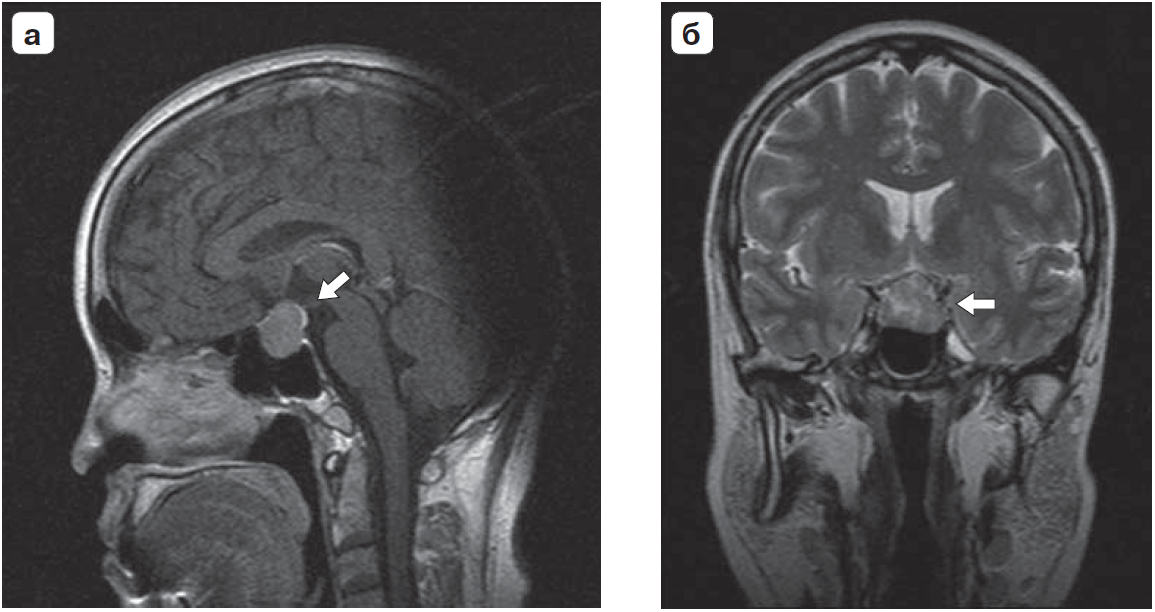

1. Рис.1а. МРТ гипофиза: макроаденома гипофиза, сагиттальный срез. | |

2. Рис.1б. МРТ гипофиза: макроаденома гипофиза, фронтальный срез. | |

6. Fig. 1. MRI of the pituitary gland: a - pituitary macroadenoma, sagittal section; b - pituitary macroadenoma, frontal section. | |